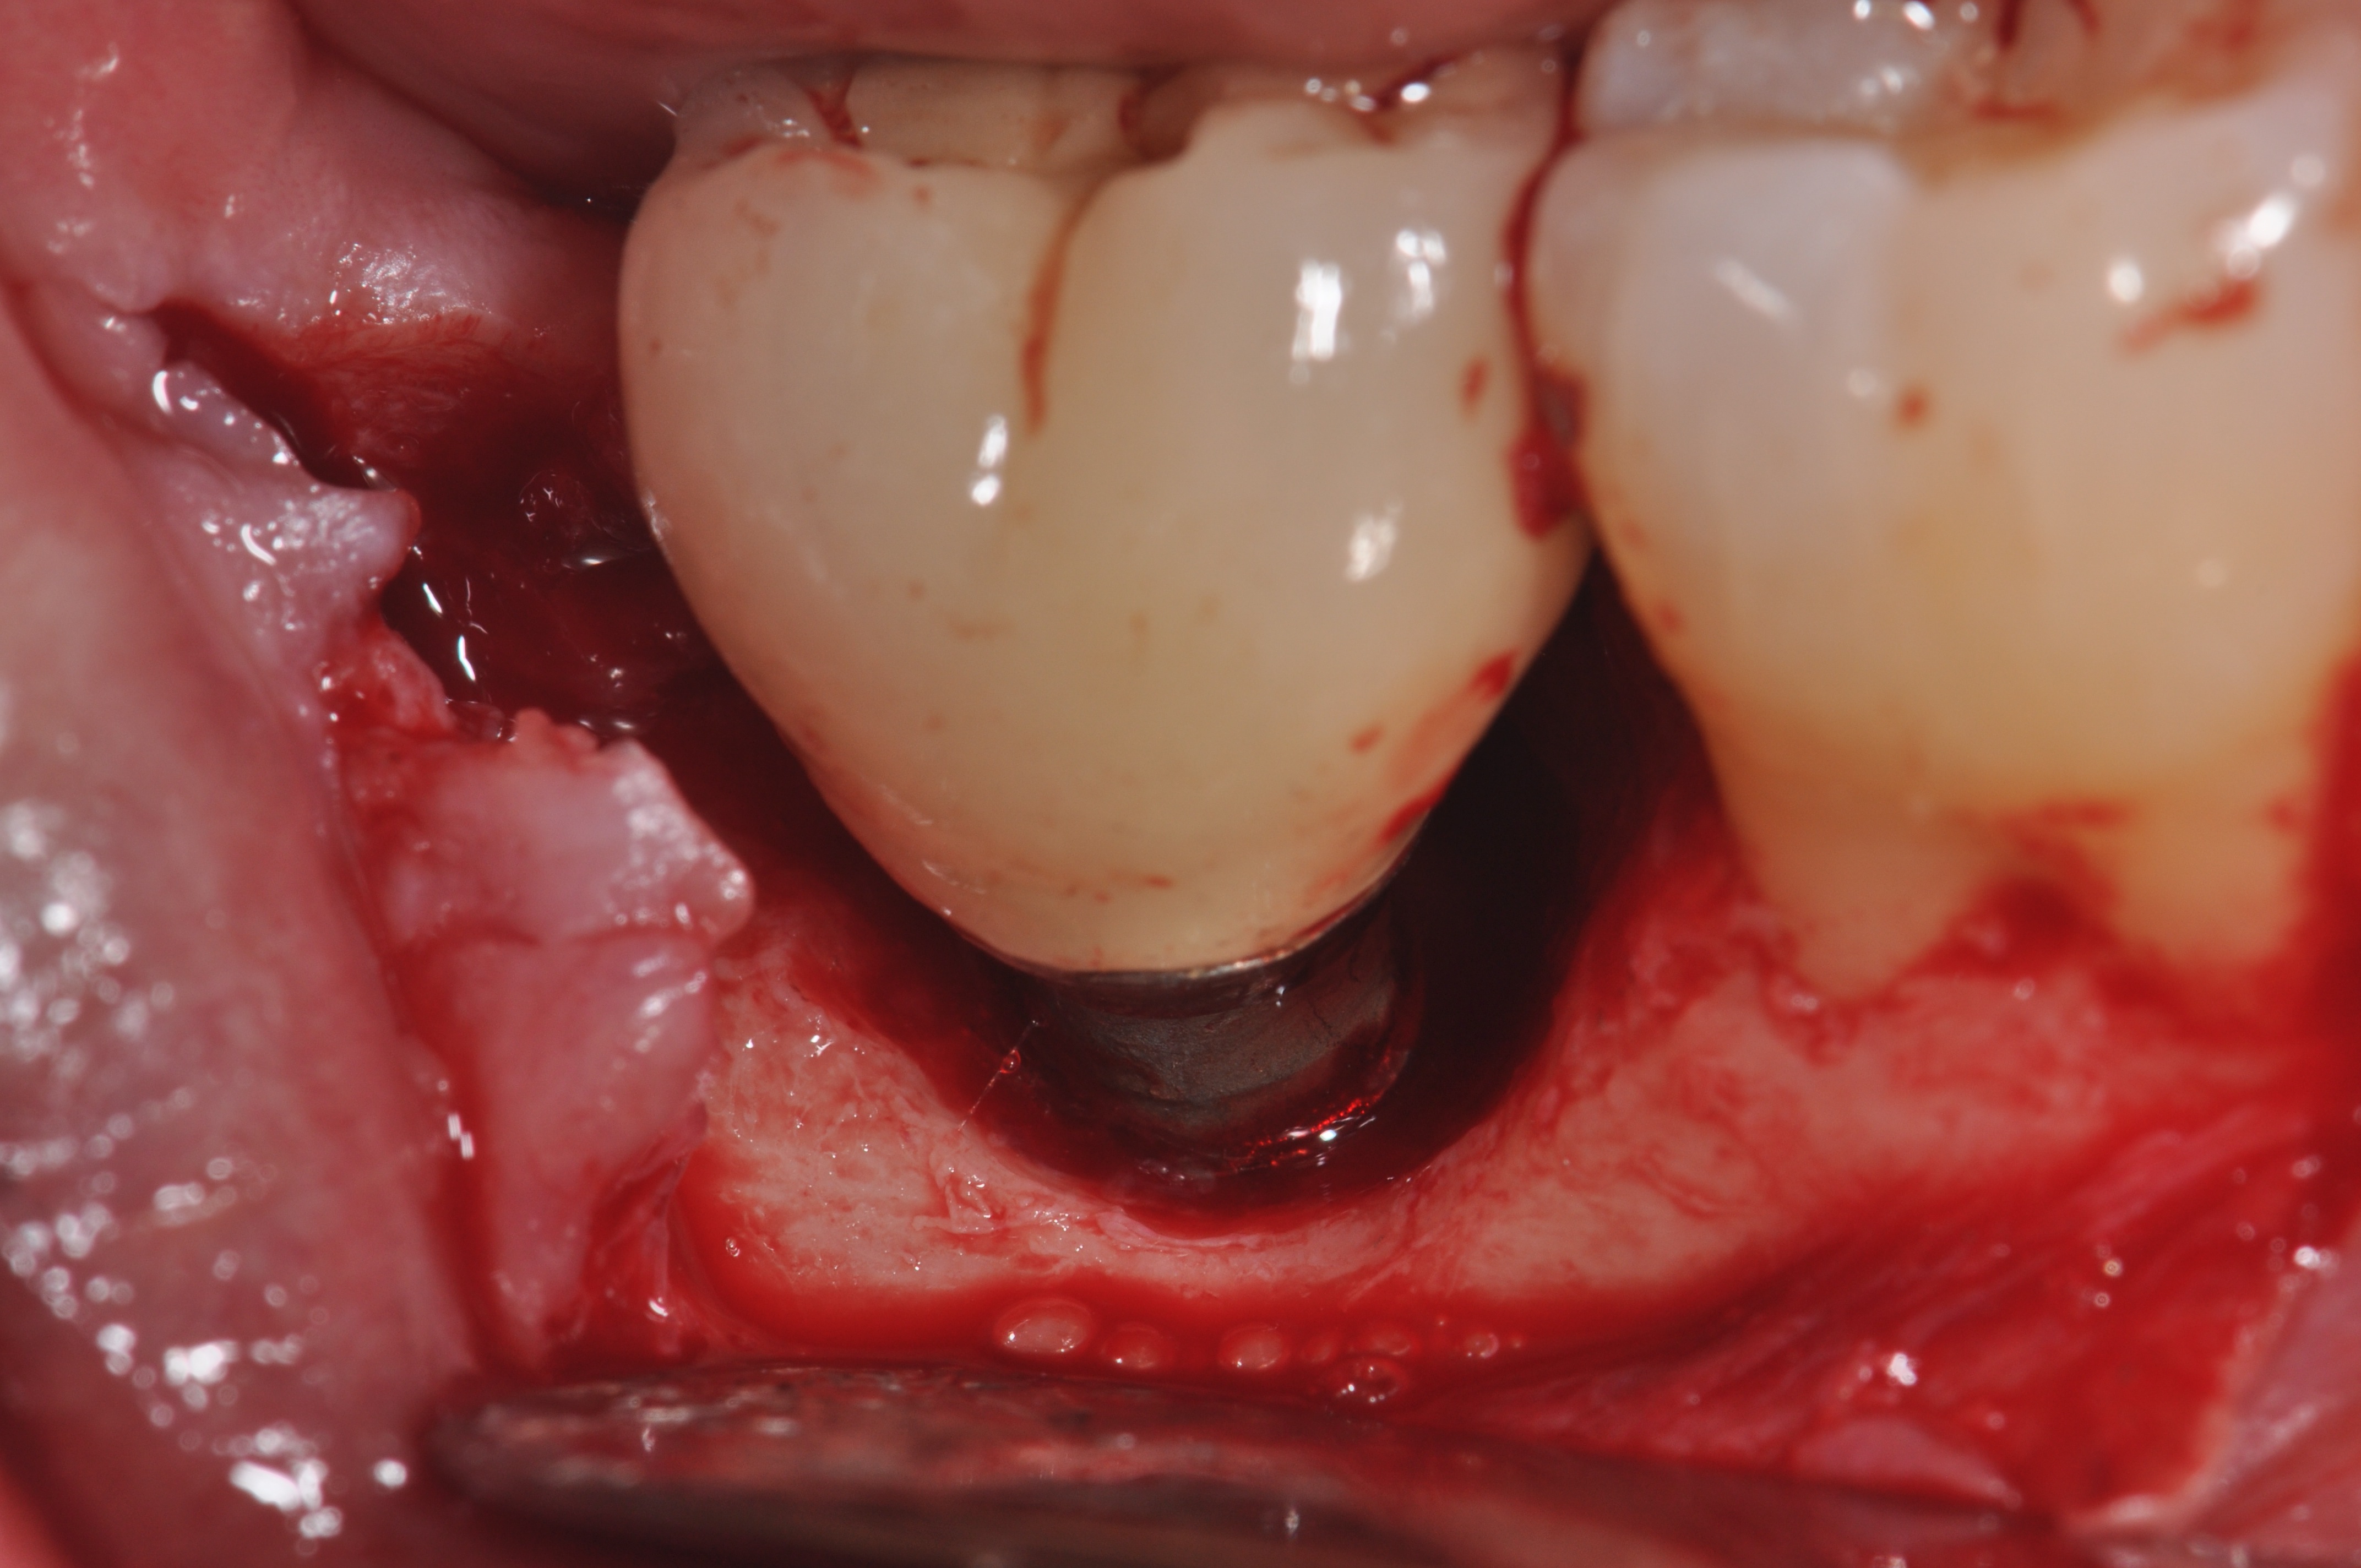

Clinical exposure of a circumferential lesion that demonstrates 3 mm of bone loss. No cement was present, suggesting that the lesion was of bacterial origin. Surface decontamination included citric acid.

Figure 2